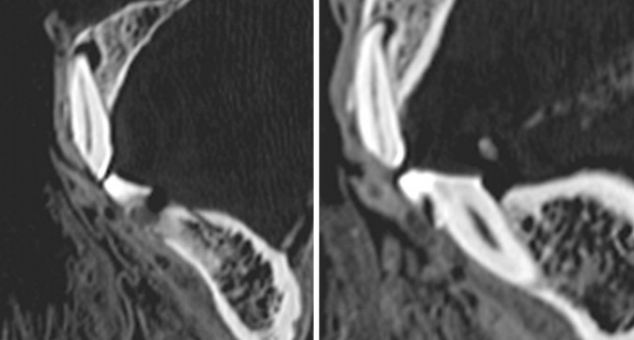

CT片顯示了木乃伊左邊第一顆門牙(左圖)和右邊第二顆門牙(右圖)的磨損狀況。